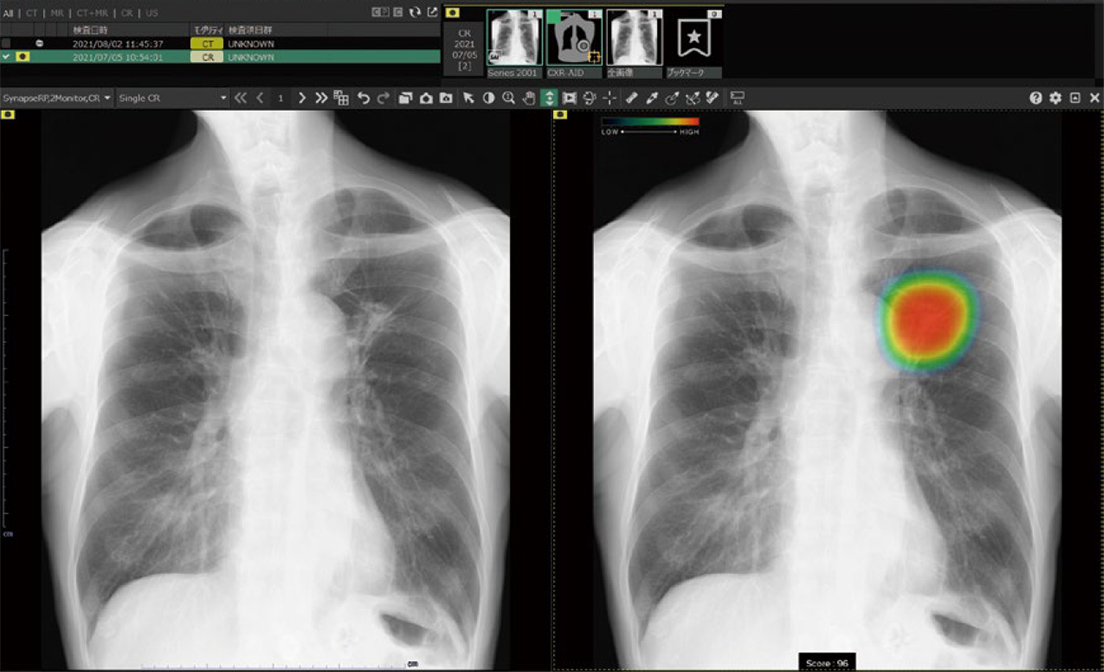

CXR-AID